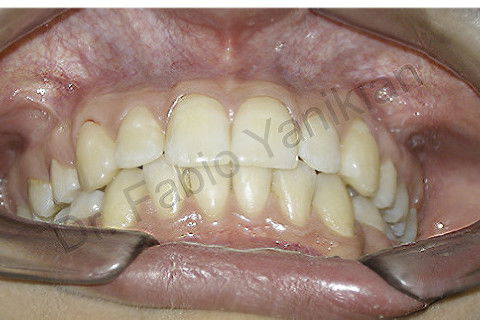

Foto frontal inicial

Foto frontal final

Paciente CL I com apinhamento superior e inferior

Evolução clínica: exo dos 4 prés, alinhamento e nivelamento, não foi necessario fazer RAS e RAI mas perda de ancoragem nos 4 quadrantes para fecar os espaços.